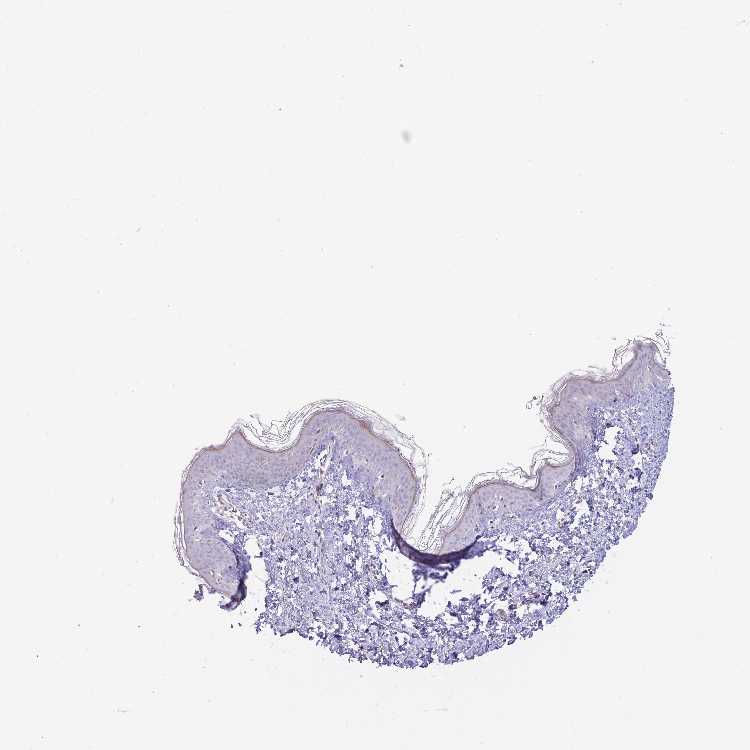

SKIN 1 - Antibody stainingi

Antibody staining in the annotated cell types in the current human tissue is reported as not detected, low, medium, or high, based on conventional immunohistochemistry profiling in selected tissues. This score is based on the combination of the staining intensity and fraction of stained cells.

Each image is clickable and will lead to virtual microscopy that enables deeper exploration of all samples and also displays staining intensity scores, fraction scores and subcellular localization as well as patient and tissue information for each sample.

Antibody HPA049064

Langerhans Not detected

Fibroblasts Not detected

Keratinocytes Not detected

Melanocytes Low

SKIN 2 - Antibody stainingi

Epidermal cells Low